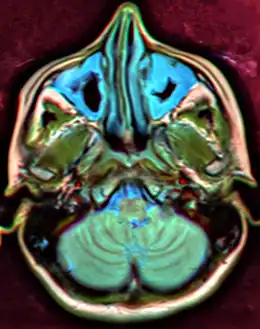

Illustration depicting sinusitis, note the fluid in the sini